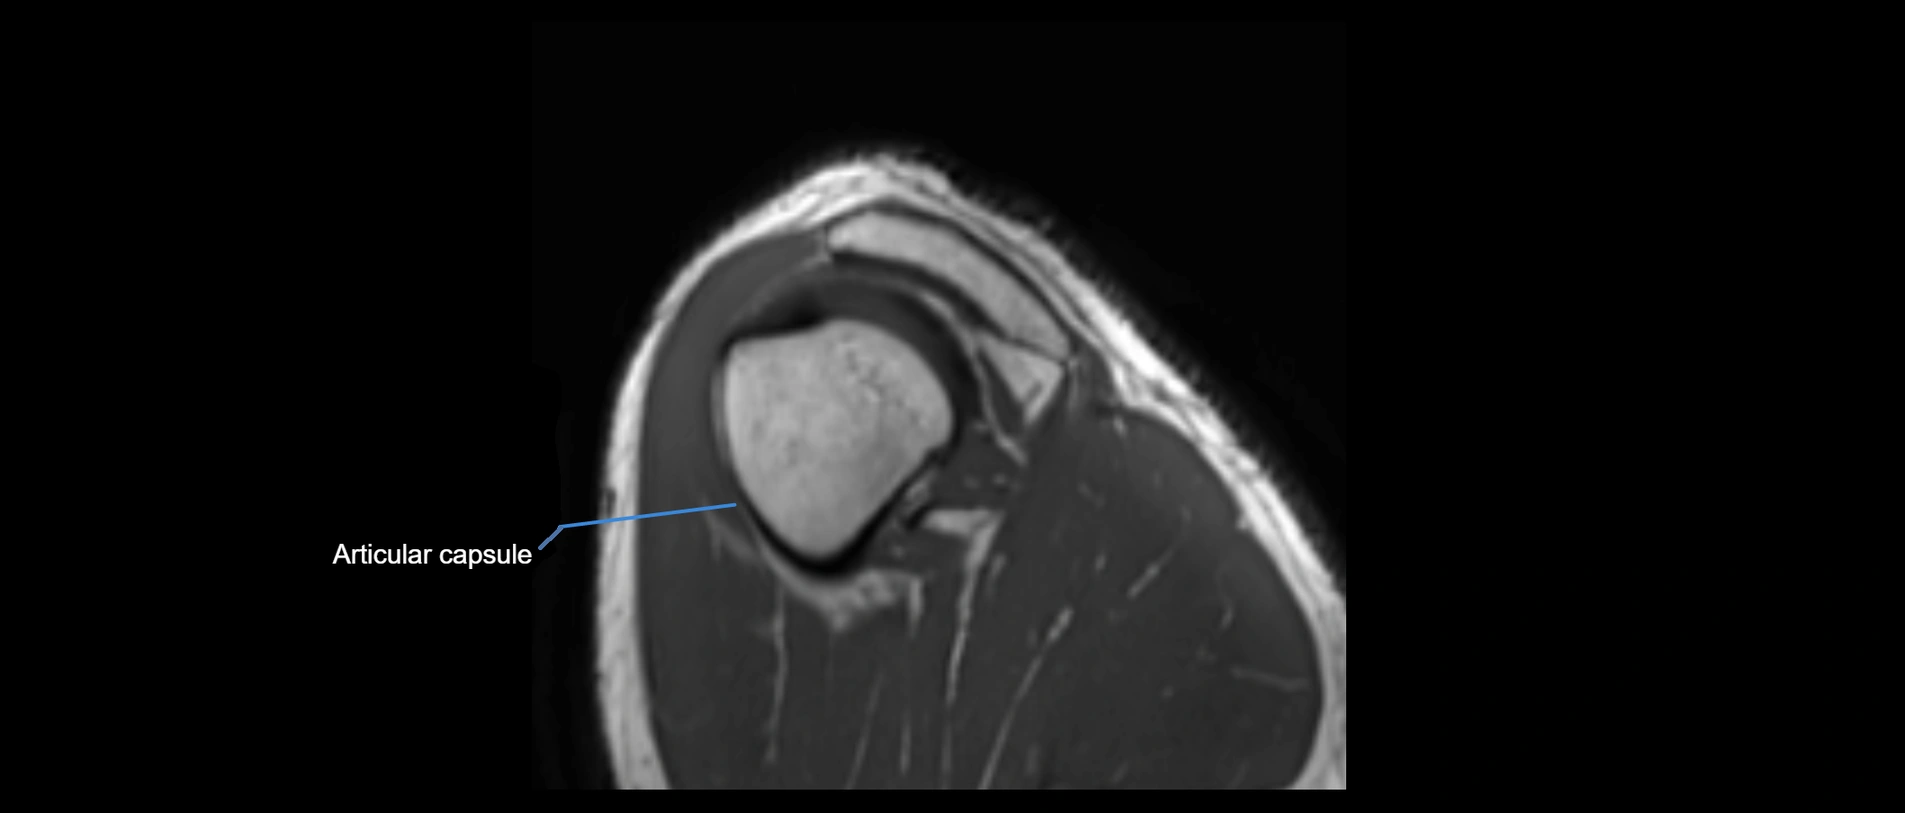

MRI images

image